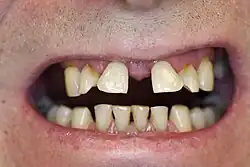

Die häufigsten Ursachen für eine Zahnwanderung sind Lockerungen der Zähne bei Parodontalerkrankungen. Oft treten diese Zahnwanderungen noch vor einer spürbaren Zahnlockerung auf. Dabei ist der Zahnhalteapparat, mittels dessen die Zähne im Kieferknochen verankert sind, bereits deutlich zerstört, die knöcherne Verankerung der Wurzeln ist insuffizient. Ein typisches Bild ist dabei die Auffächerung (Kippungen) der sechs oberen Frontzähne nach vestibulär (zum Mundvorhof hin), die durch den Zungendruck oder durch das Anschwellen parodontaler Gewebe während der aktiven Entzündungsphase nach vorne kippen.[2] Dadurch vergrößert sich der Radius des Zahnbogens und es treten charakteristische Lücken zwischen den Oberkiefer-Frontzähnen auf. Weiter gefördert wird diese Zahnwanderung durch den Druck der Unterkiefer-Frontzähne von palatinal, insbesondere bei einem sogenannten tiefen Biss. Ausgeprägte Hyperplasien, beispielsweise nach Hydantoineinnahme, können Zahnwanderungen verursachen.[3]

Eine weitere Ursache für eine Zahnwanderung bzw. Zahnverschiebung kann auch Zahnverlust sein, beispielsweise durch notwendig gewordene Extraktionen (Zahnentfernungen). Bleibt die dadurch entstandene Zahnlücke unversorgt, können sich die Nachbarzähne im Sinne eines kompensatorischen Lückenschlusses allmählich zur Lücke zu bewegen. Alternativ kommt es zu Kippungen der Nachbarzähne.